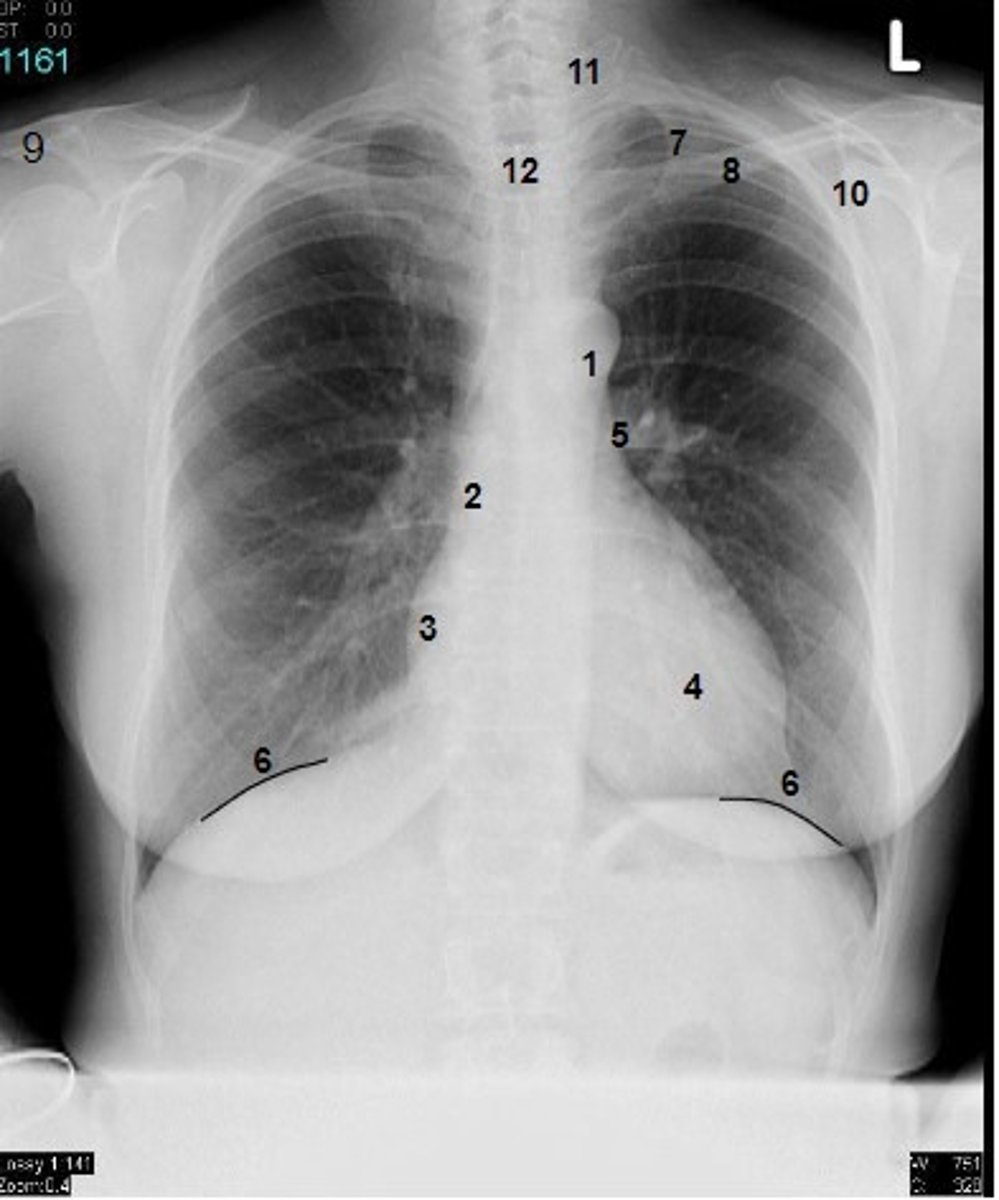

1

at what number is the arch of aorta?

2

at what number is the superior vena cava

3

at what number is the right atrium

4

at what number is the left ventricle

5

at what number is the primary bronchus

6

at what number is the dome of diaphragm

7

at what number is the first rib

8

at what number is the clavicle

9

at what number is the acromion of scapula

10

at what number is the coracoid process of scapula

11

at what number is the transverse process of vertebra

12

at what number is the spinous process of vertebra